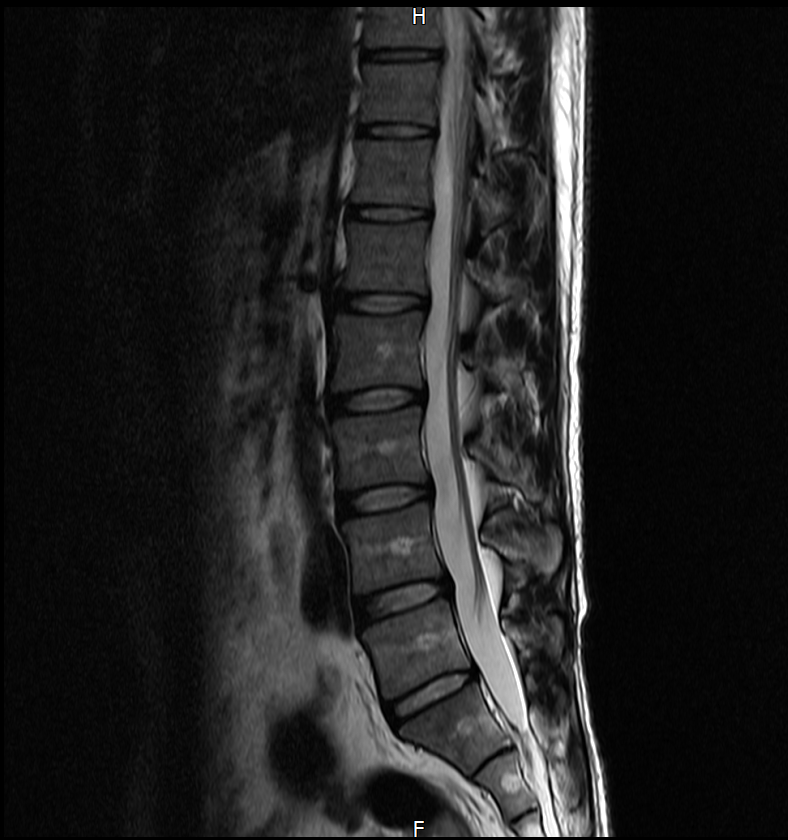

※우리들병원 (신경외과 대표원장) : 경추,요추 MRI 촬영했고 요추는 매우 건강하고 경추에는 일자목에 퇴행성 디스크가 보이지만 한쪽팔에 저림이나 힘빠짐을 유발할 정도는 절대아니고, 다른 원인을 찾아야한다고 했습니다.

※분당서울대병원 재활의학과 : 근전도검사 이상없음, 경추 요추 MRI를 봐도 근골격계 문제로 보기 어렵다. 신경계 문제도 아니다.

3명이 디스크가 아니라고 하는데 1명이 디스크일수 있다고 하니까 조금 어렵습니다. 경추디스크가 약간은 있으니 팔저림은 설명할수 있다해도 다리저림은 설명이 안됩니다.. MRI 결과상 요추는 매우 건강하다고 하셨거든요.

아래는 저의 경추과 요추 MRI 사진 첨부합니다.